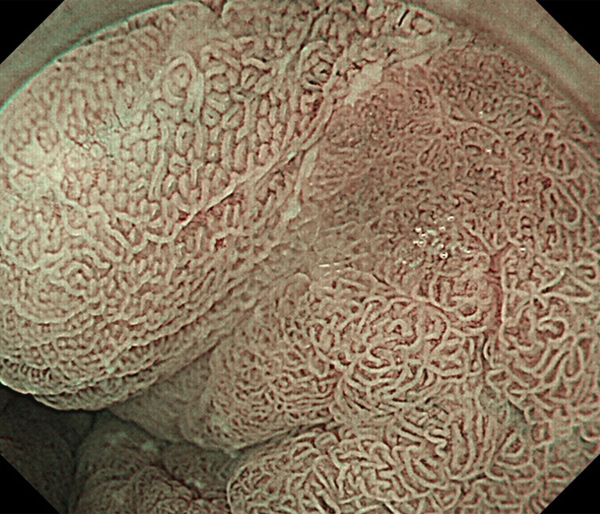

内視鏡所見と病理組織像の1対1対応が可能な症例を公募いたします。主にLSBEに発生した早期癌(HGDを含む)を対象としますが、興味深い症例であればSSBE癌でも結構です。採否は世話人へご一任ください。

症例呈示希望者は応募用紙に記入の上、代表的な内視鏡(2枚)、切除標本(新鮮、固定)、切り出し図、マッピング、代表的組織像とともに、Barrett 食道研究会事務局 barrett.shinshu@gmail.comへお申し込み下さい(10MB以下でお願い致します)。

特に、本邦では極めて稀なlong segment Barrett’s esophagus(LSBE)から発生した早期癌は、診断に難渋する場合も多く、欧米ではランダム生検による検出が標準的とされています。背景のBarrett食道もろとも全体を内視鏡切除+ラジオ波焼灼する欧米と異なり、ESDで内視鏡的な局所切除が基本の本邦では、存在診断+範囲診断(特に水平)を的確に行うことが不可欠です。

そのためには、一流の病理医による組織学的診断とエキスパート内視鏡医による拡大内視鏡像との一対一対応を徹底的に行うことで、『本来、見えないであろう拡大所見の先にある組織構築像が診えてくる』所まで内視鏡診断レベルを上げていく必要があります。その実現には、一対一対応を追究した症例(特にLSBE発生例)1例でも多く経験するしかありません。本研究会でBarrett食道腺癌(LSBE発生早期病変)を共に学び、拡大内視鏡像の一歩先を診るスキルを習得しましょう!一人でも多くの皆様のご参加をお待ちしています。